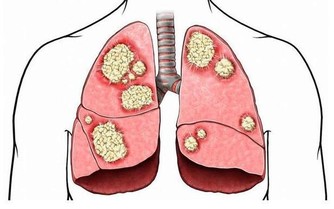

但是醫學研究發現痛風產生的尿酸結石等病變早期主要影響腎小管的重吸收功能,使人體濃縮尿液的能力下降,這是在悄無聲息損傷痛風患者的腎臟,而且並不一定會反應為血肌酐升高。所以,在腎內科一般都認為痛風都會百分百引發腎臟損害!